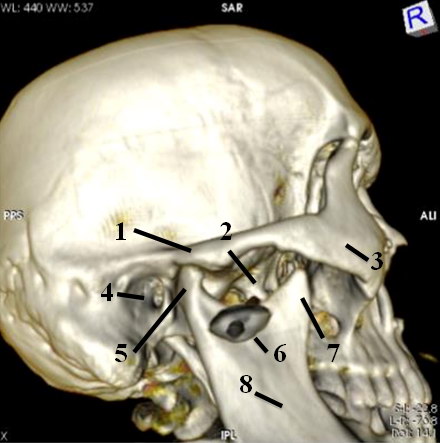

Анатомические особенности: фотографии ямок черепа, височной и подвисочной крылонебной